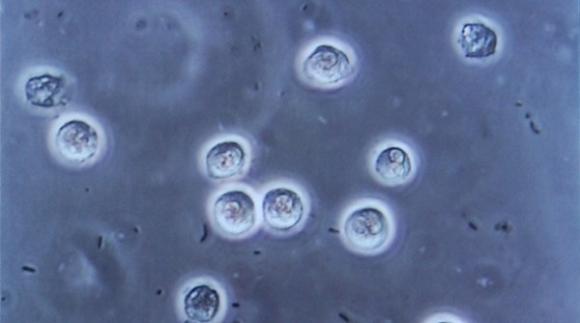

Infecciones urinarias provocadas por el uso de sondas vesicales se podrán evitar a partir de una invento desarrollado por un médico porteño. Foto: Steven Fruitsmaak / Wikimedia Commons Las sondas vesicales son...